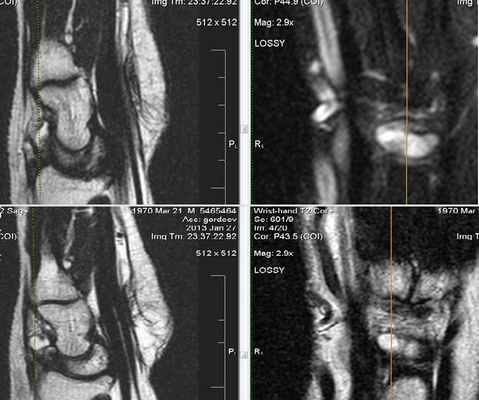

Все виды повреждения кисти можно разделить на несколько групп. Начнем с МР-диагностики травматических повреждений кисти и а.При клиническом обследовании больных с ушибами лучезапястного сустава и кисти, как правило, определяются болезненность при пальпации, увеличение объема окружающих мягких тканей, а объективно и рентгенологически изменения отсутствуют. Наиболее часто встречаются ушибы метаэпифиза лучевой и локтевой костей, а также полулунной и ладьевидной костей. Ушибы (контузионные поражения) кисти определяются только при МРТ-исследовании, особенно хорошо видно на программах с подавлением сигнала от жира. Морфологически ушиб кости проявляется нарушением целостности трабекул костной ткани с кровоизлиянием и отеком костного мозга. Однако, несмотря на повреждение трабекул костной ткани, рентгенологические исследования, включая КТ, не позволяют обнаружить патологические изменения. Клинические проявления у пациента: боль и ограничение движений после падения на вытянутую руку 4 месяца н

При клиническом обследовании больных с ушибами лучезапястного сустава и кисти, как правило, определяются болезненность при пальпации, увеличение объема окружающих мягких тканей, а объективно и рентгенологически изменения отсутствуют. Наиболее часто встречаются ушибы метаэпифиза лучевой и локтевой костей, а также полулунной и ладьевидной костей. Ушибы (контузионные поражения) кисти определяются только при МРТ-исследовании, особенно хорошо видно на программах с подавлением сигнала от жира. Морфологически ушиб кости проявляется нарушением целостности трабекул костной ткани с кровоизлиянием и отеком костного мозга. Однако, несмотря на повреждение трабекул костной ткани, рентгенологические исследования, включая КТ, не позволяют обнаружить патологические изменения.

Клинические проявления у пациента: боль и ограничение движений после падения на вытянутую руку 4 месяца назад.

Перелом ладьевидной кости с явлениями асептического некроза проксимального полюса и, связанного с ним, остеоартрита. Ладьевидный перелом обычно происходит из-за падения на вытянутую руку, которое приводит к гиперэкстензии лучезапястного сустава.

Аваскулярный (асептический) некроз нередко сопутствует переломам проксимальной части ладьевидной и переломам полулунной кости, а также неадекватно репонированным и иммобилизированным переломам этих костей. Основная причина – нарушение трофики участка кости при повреждении питающих артерий.

Методом выбора в диагностике и стадировании остеонекроза костей кисти является МРТ.